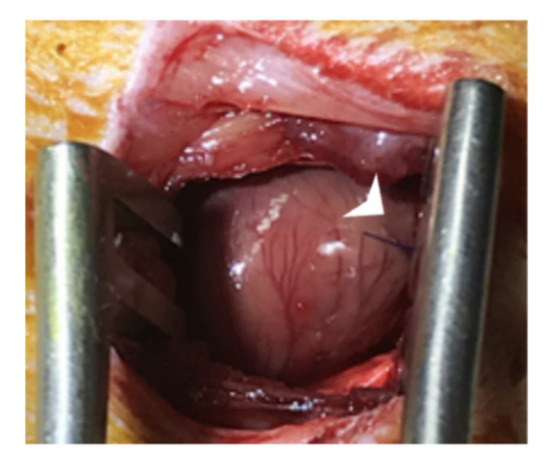

2.6. Chronic Myocardial Infarction (MI) and Cell + Nanoparticle Transplantation